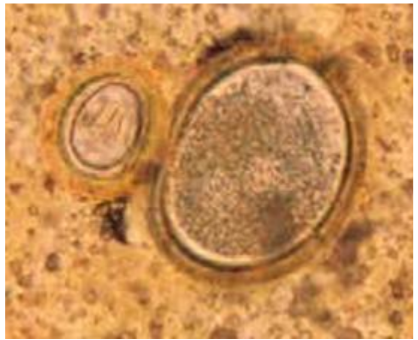

Taenia spp. and A. lumbricoides

A. lumbricoides (fertile egg, decorticated egg)

A. lumbricoides